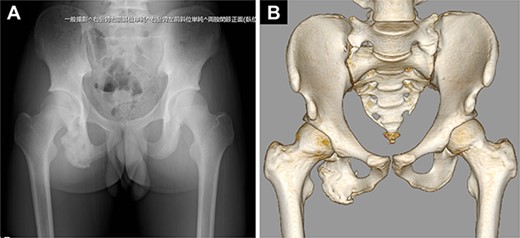

His hamstring strength measured using a hand-held dynamometer recovered to 80% of that on the unaffected side by 6 months after surgery and was maintained thereafter (Table 1). Pelvic images showed bony fusion of the avulsed fragment (Fig. 5). One year after the surgery, he returned to his preinjury competitive level and broke his own record for short-distance running. His Perth Hamstring Assessment Tool [5] score was 100 points (100%).

Postoperative images of the pelvis. (A) Plain radiograph. (B) Computed tomography scan.